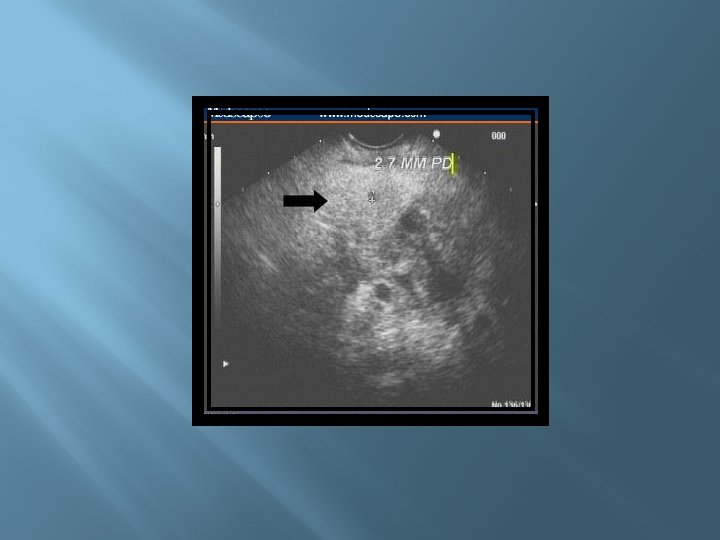

� Ultrasonido � Mayor sensibilidad para detectar el lodo biliar o microlitiasis � Imagen patognomónica Páncreas hipoecoico y aumentado de tamaño No se observa en 35% de los pacientes Se observa en sólo 25 a 50% de los pacientes con pancreatitis aguda